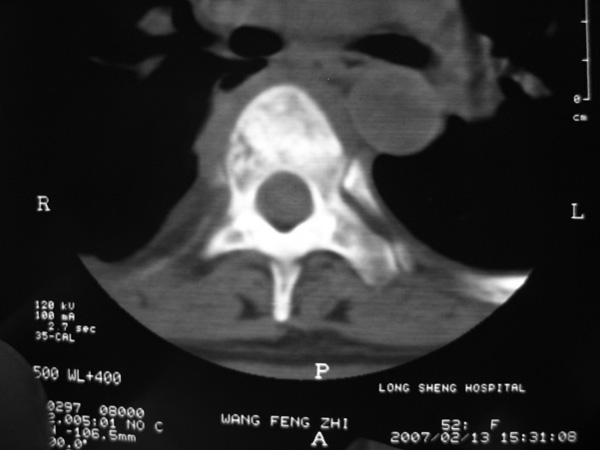

女,45岁,胸背部疼痛2个月。t6、7胸椎病变。

椎旁肿胀的软组织内可见气泡影,对脊柱的化脓性和结核性的鉴别有帮助吗?

胸椎结核伴冷脓肿形成且侵入椎管。

胸椎结核与脊柱椎体化脓性脊柱炎,从影像特点很难鉴别,本例具有二者的共性特点,建议结合临床鉴别以下,我考虑:1 化脓性脊柱炎.2 胸椎结核.原因:1 椎旁脓肿内含气泡.2 椎体溶骨性破坏,但未见死骨.

胸椎体骨质破坏伴死骨形成,椎周环状软组织肿胀,范围较长,考虑胸椎结核伴冷脓肿形成。鉴别;1转移性肿瘤;椎弓根骨质破坏多见,软组织肿块局限。椎间隙尚存。有原发肿瘤病史。2,淋巴瘤;骨质破坏 然骨皮质轮廓线尚存,当椎管骨示环状软组织影时有一定特异性。病变较局限。建议mri增强,观察冷脓肿与软组织肿块很有帮助。

胸椎结核与脊柱椎体化脓性脊柱炎,从影像特点很难鉴别,本例具有二者的共性特点,建议结合临床鉴别以下,我考虑:1 胸椎结核.2 化脓性脊柱炎.原因: 椎体溶骨性破坏,但未见死骨.我认为大家说的气泡是假象。